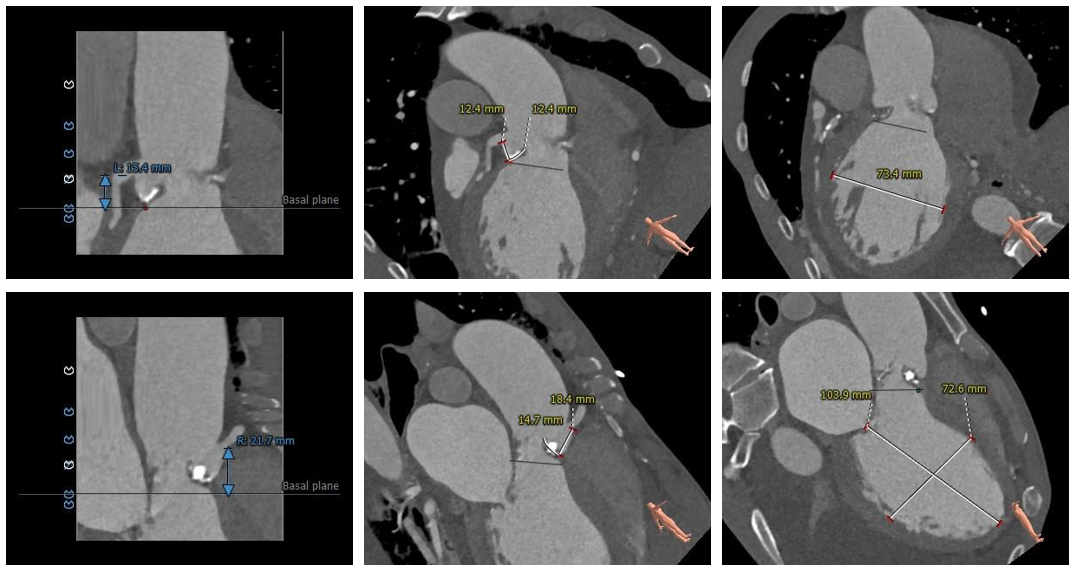

术前CT评估

•三叶式主动脉瓣,瓣环径为33.9mm,瓣环明显增大,瓣叶增厚伴重度钙化,钙化主要分布于瓣叶边缘,以右冠瓣为著;

•冠脉开口高度可,切线角度测量未见冗长瓣叶;

•瓦氏窦、窦管交界内径尚可,升主动脉扩张;

•左室腔内径明显增大,心室壁厚度尚可;

•瓣环水平夹角为62°,主动脉弓宽度、角度尚可;升主动脉轻度扭曲;

主动脉根部测量

瓣上结构测量

冠脉阻挡风险及左室大小评估